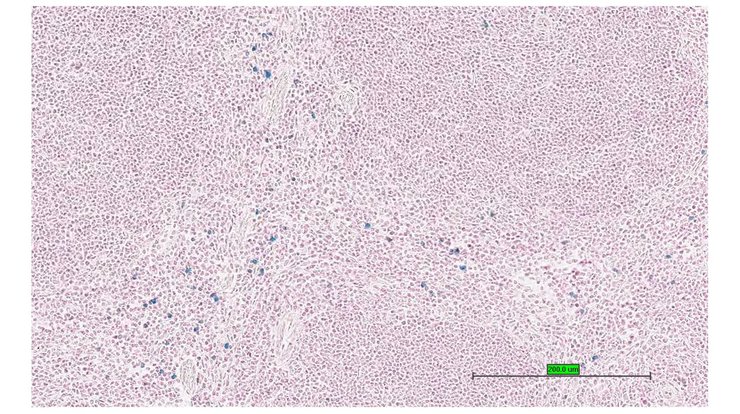

TS28: spleen Present UC Davis_1883589

Specimen UC Davis_1883589: postnatal adult; Prf1tm1.1(KOMP)Vlcg/Prf1+ (more )